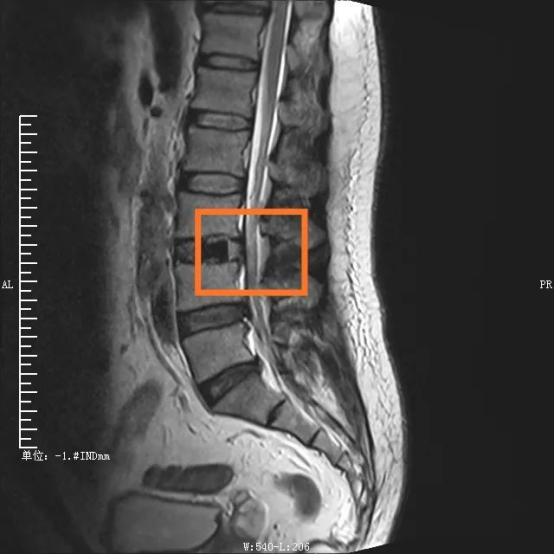

手術部位術前/術后對比圖

在外科醫生眼中,衡量一臺手術是否成功、是否屬于微創范疇,術中的出血量、組織損傷、手術時間以及術后康復時間都是重要考量因素。傳統腰椎手術從后方入路,需要切開分離肌肉組織,手術創傷大,時間長,出血量多??紤]到傳統手術對患者肌肉等組織損傷較大,且手術費用及住院時間增加,脊柱脊髓專業組決定采取更安全高效的OLIF手術。

“OLIF手術采用側方入路,手術區域在椎管前方,不破壞后方結構,不分離脊柱后方肌肉,極大地減少了組織損傷?!编嚴捉榻B,這種技術巧妙在于,充分了利用腹膜后主動脈與腰大肌前緣之間的自然間隙,到達目標椎體斜外側,結合神經外科顯微手術技術,切除病變椎間盤,實現椎間融合。若手術順利,術中患者出血僅20ml左右,患者術后2天就能下床活動,3天即可出院。